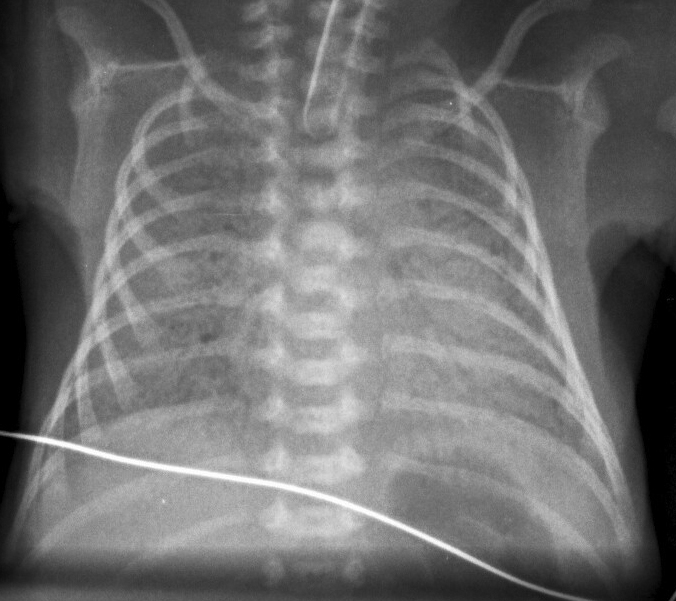

Chest X Ray Findings In Rds . Respiratory distress syndrome is caused by pulmonary surfactant deficiency in the lungs of neonates, most commonly in. chest radiography, being the most widely available imaging modality with a high degree of sensitivity and relatively. in respiratory distress syndrome (rds), the classic chest radiographic findings consist of pronounced hypoaeration, bilateral fine granular opacities in the.

Respiratory distress syndrome is caused by pulmonary surfactant deficiency in the lungs of neonates, most commonly in. chest radiography, being the most widely available imaging modality with a high degree of sensitivity and relatively. in respiratory distress syndrome (rds), the classic chest radiographic findings consist of pronounced hypoaeration, bilateral fine granular opacities in the.